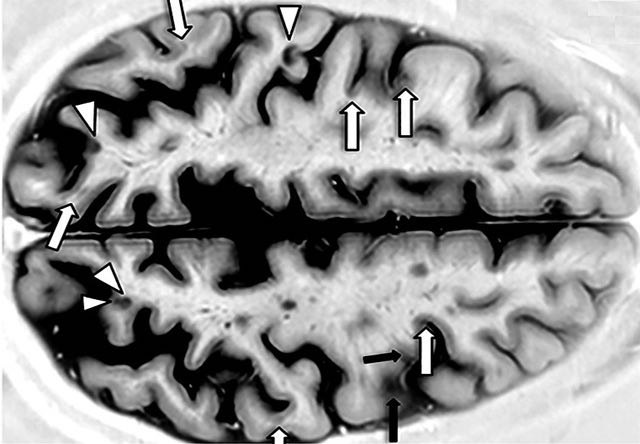

Ученые провели финальное испытание лекарства, которое предназначено для замедления развития рассеянного склероза. Они выяснили, что сипонимод способен затормозить деградацию нервных волокон у пациентов. Препарат сипонимод замедляет деградацию нервной ткани и общее ухудшение состояния у пациентов, страдающих вторично-прогрессирующим склерозом. При рассеянном склерозе собственные иммунные клетки человека разрушают миелиновые оболочки нервных окончаний. Это приводит к появлению у больных разнообразных неврологических симптомов, таких как нарушение координации, ухудшение зрения, депрессия, снижение интеллекта. Чаще всего заболевание имеет прерывистый характер, то есть периоды проявления симптомов сменяются периодами частичного или полного восстановления. Однако через 10-20 лет такого течения болезни рассеянный склероз более чем в половине случаев переходит в тяжелую форму — вторично-прогрессирующий рассеянный склероз, который характеризуется постепенным ухудшением состояния больного.